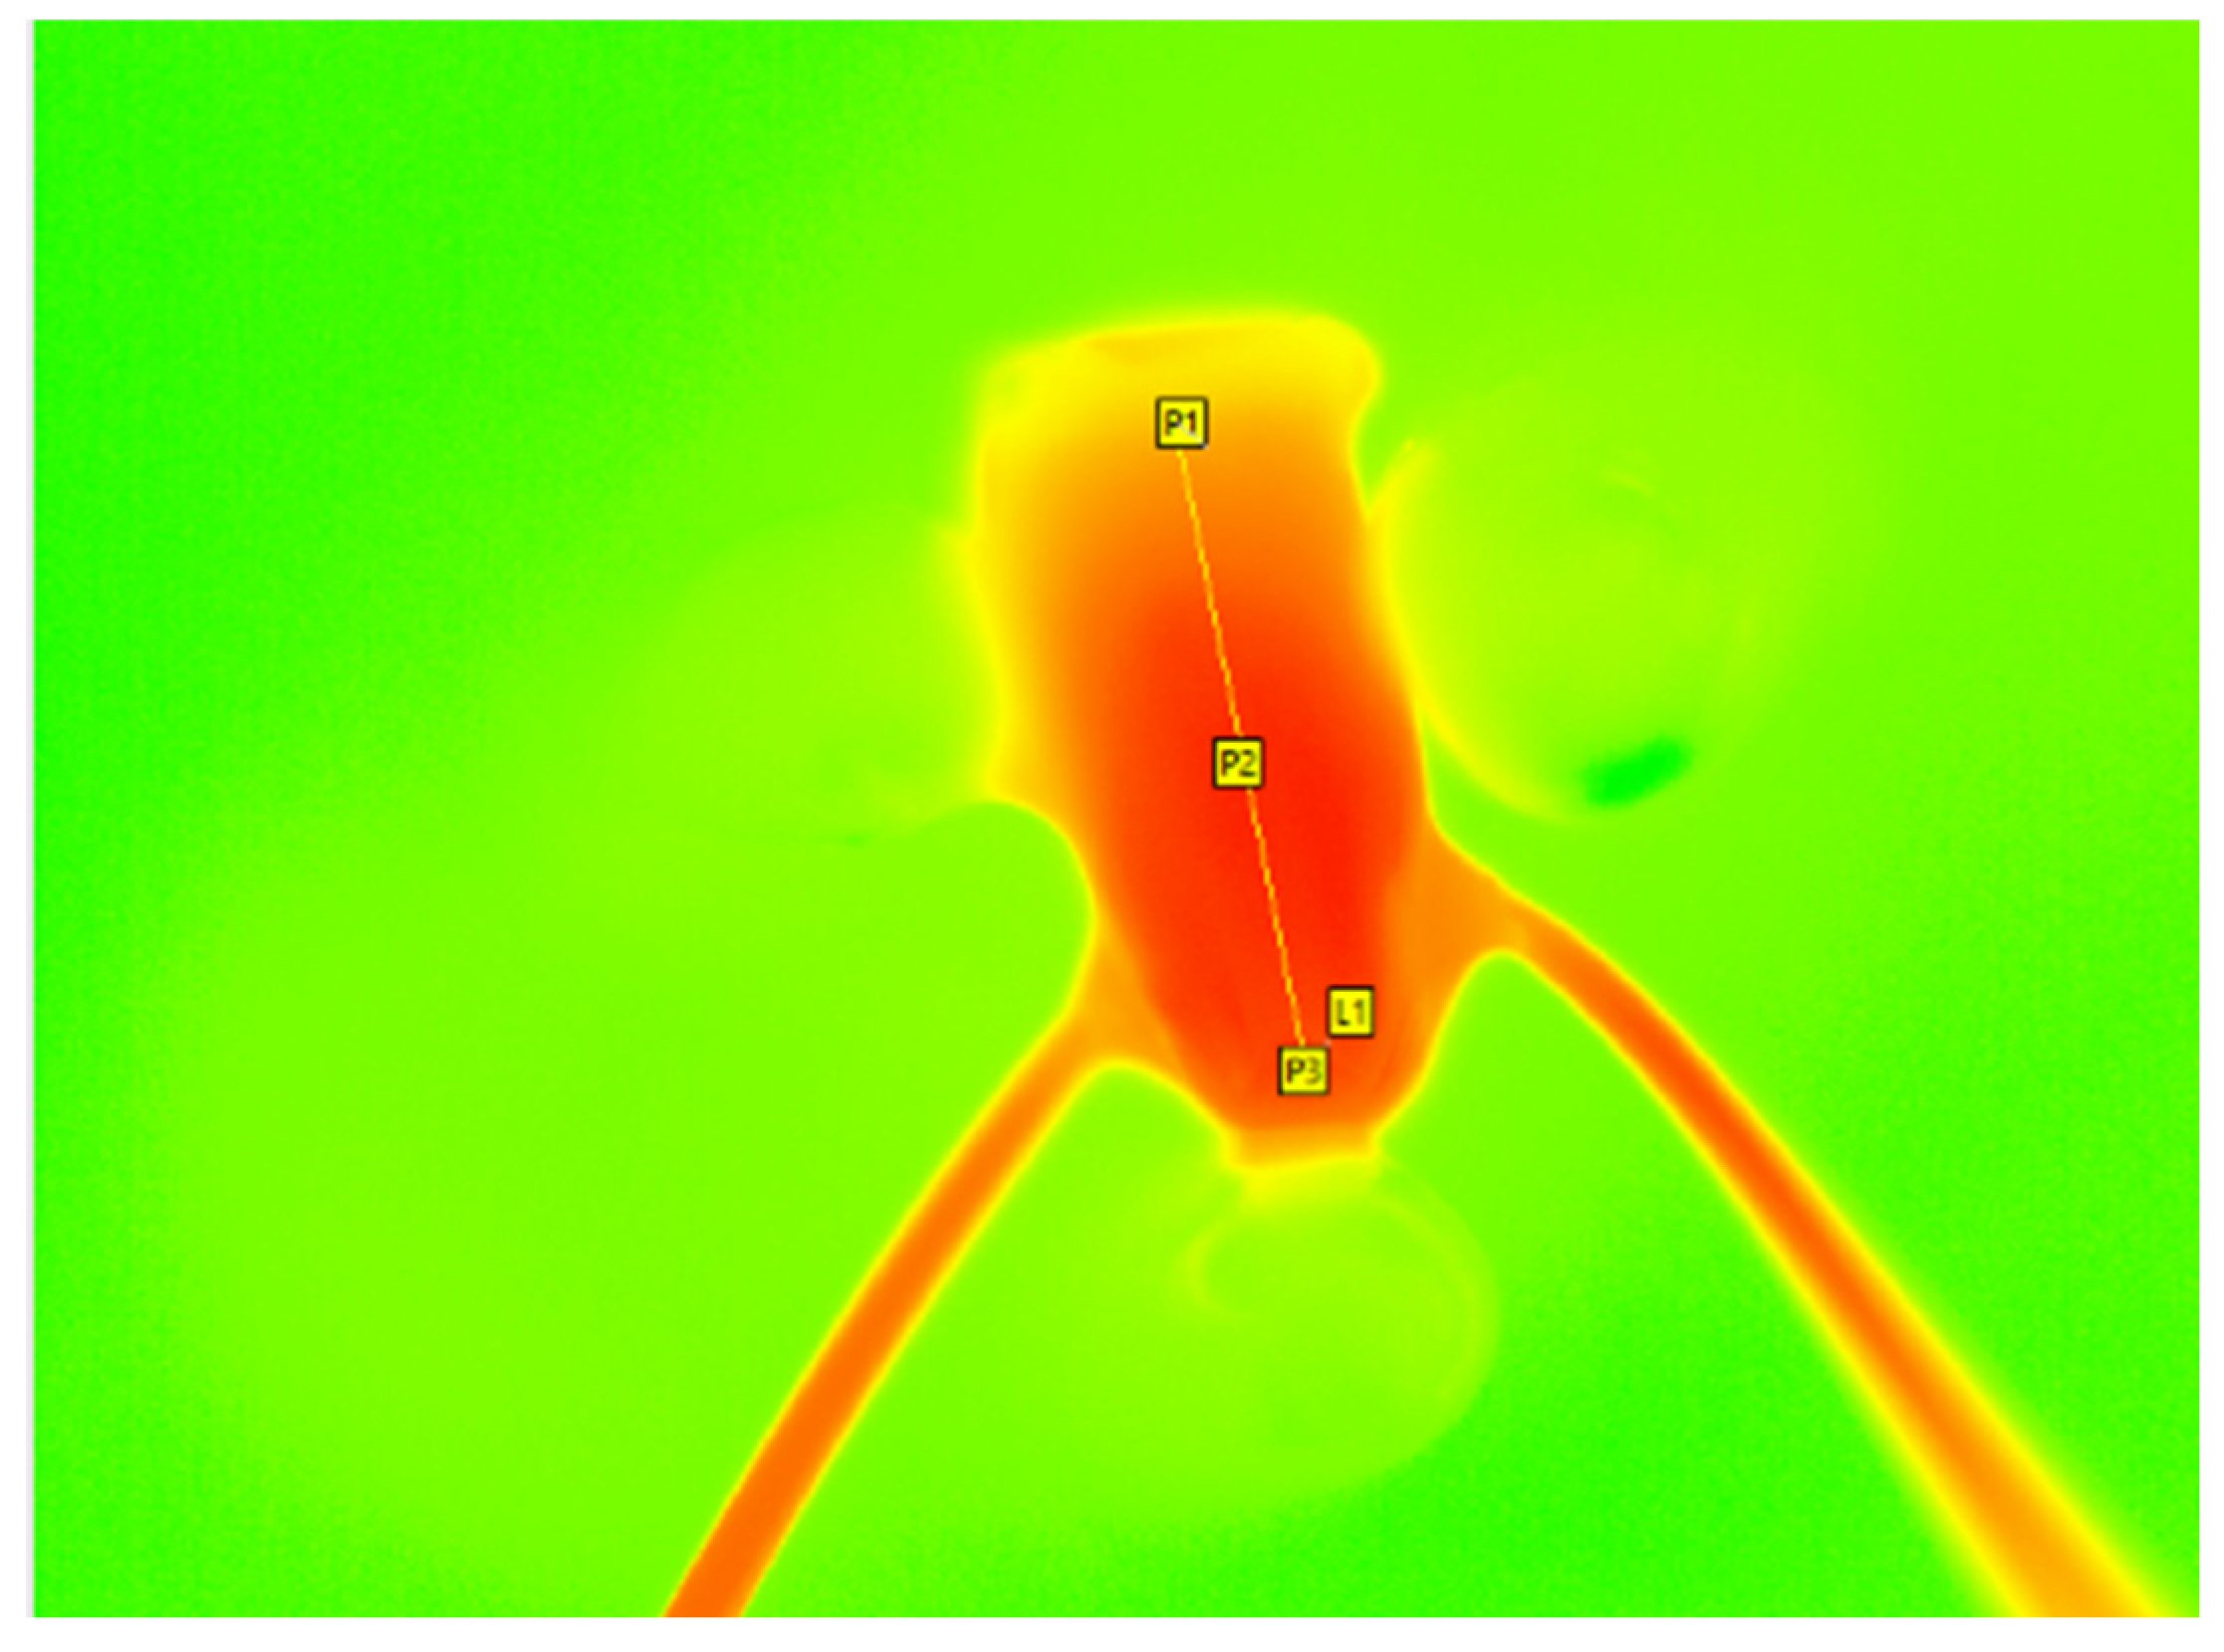

A temperature–time diagram was created using the IRBIS 3.1 plus software (InfraTec GmbH Infrarotsensorik und Messtechnik, Dresden, Germany), and the data was displayed in an Excel sheet (Microsoft Office Professional Plus 2016, Microsoft, Redmond, DC, USA). The data provided the initial temperature (T0), the maximum temperature (Tmax), the latency time until the maximum temperature is reached, and the delta between Tmax and T0. The data was not normally distributed. The values were analyzed statistically using the Kruskal–Wallis test. If there was a significant difference between the groups (p < 0.05), the Mann–Whitney pairwise test using the sequential Bonferroni procedure was performed. p-values < 0.05 was considered statistically significant. For the statistical analysis, three measuring points (P1, P2, and P3) were set individually in the tooth samples, located in the coronal, middle, and apical parts of each sample. To measure the mean temperature, the points were connected using a line (L1, Figure 2). To illustrate the results, box plot diagrams were created to demonstrate the median, first and third quartiles, and the minimum and maximum values. Outliers were defined as values exceeding 1.5 to three times the interquartile range. These are marked as dots, whereas distant outliers are marked as asterisks.

Figure 2.

Temperature measurement using a thermal imaging camera (VarioCAM HD; InfraTec GmbH Infrarotsensorik und Messtechnik, Dresden, Germany) during obturation. The P1, P2, and P3 points are set at the coronal, middle, and apical thirds, with the line L1 connecting them.